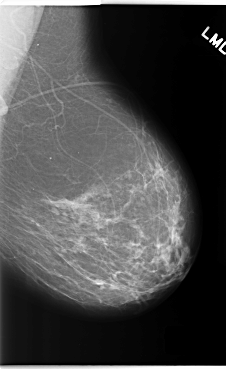

C_0214_1.LEFT_MLO

LEFT_MLO LINES 5904 PIXELS_PER_LINE 3608 BITS_PER_PIXEL 12 RESOLUTION 50 NON_OVERLAY